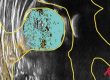

Punto 1… ¿qué busca? Se usa para ver si la cabeza del fémur está dentro del acetábulo. Hay algún bebé que nace con la cadera fuera. Por tanto, con esta indicación tiene sentido tener una ecografía en los primeros días tras el nacimiento. Pero también se emplea para ver la maduración del acetábulo (el cuenco, ver “quién es quién en la cadera infantil”). Con esta indicación nos interesa realizarla al mes de vida y, en los casos que el resultado sea “inmaduro” se repetirá al segundo y al tercer mes.